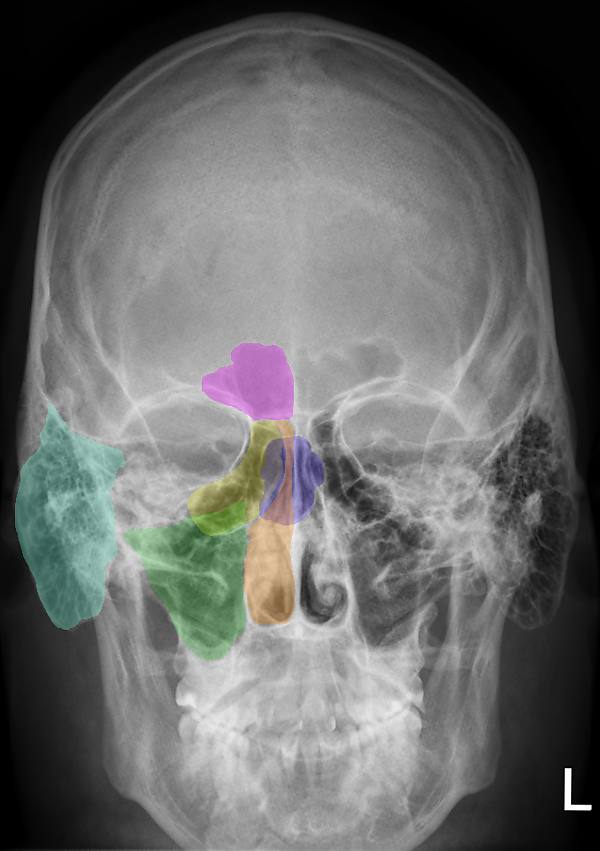

Рентгеноанатомия костей

Присутствие солей кальция в костях делает их менее «прозрачными» для лучей рентгена, чем окружающие мягкие ткани; при этом в связи с различиями в гистологической структуре компактного и губчатого вещества кости отличается и характер их рентгеновского отображения. Компактное вещество кости образует на рентгенограмме интенсивную «тень» в виде светлых полос большей или меньшей ширины, а губчатое — ячеистый, сетеподобный рисунок.

В местах соединения костей друг с другом отмечается тёмная полоса («полоса просветления») — рентгеновская суставная щель, отграниченная более светлыми линиями субхондральных отделов сочленяющихся костей. Ширина рентгеновской суставной щели зависит от толщины «прозрачного» для рентгеновских лучей суставного хряща.

Рентгенография позволяет идентифицировать «костный возраст» человека — визуализировать точки окостенения, замещение эпифизарного хряща костной тканью, сращение отделов кости (формирование синостоза). Данные возрастные особенности оссификации являются предметом изучения клинической рентгеноанатомии.